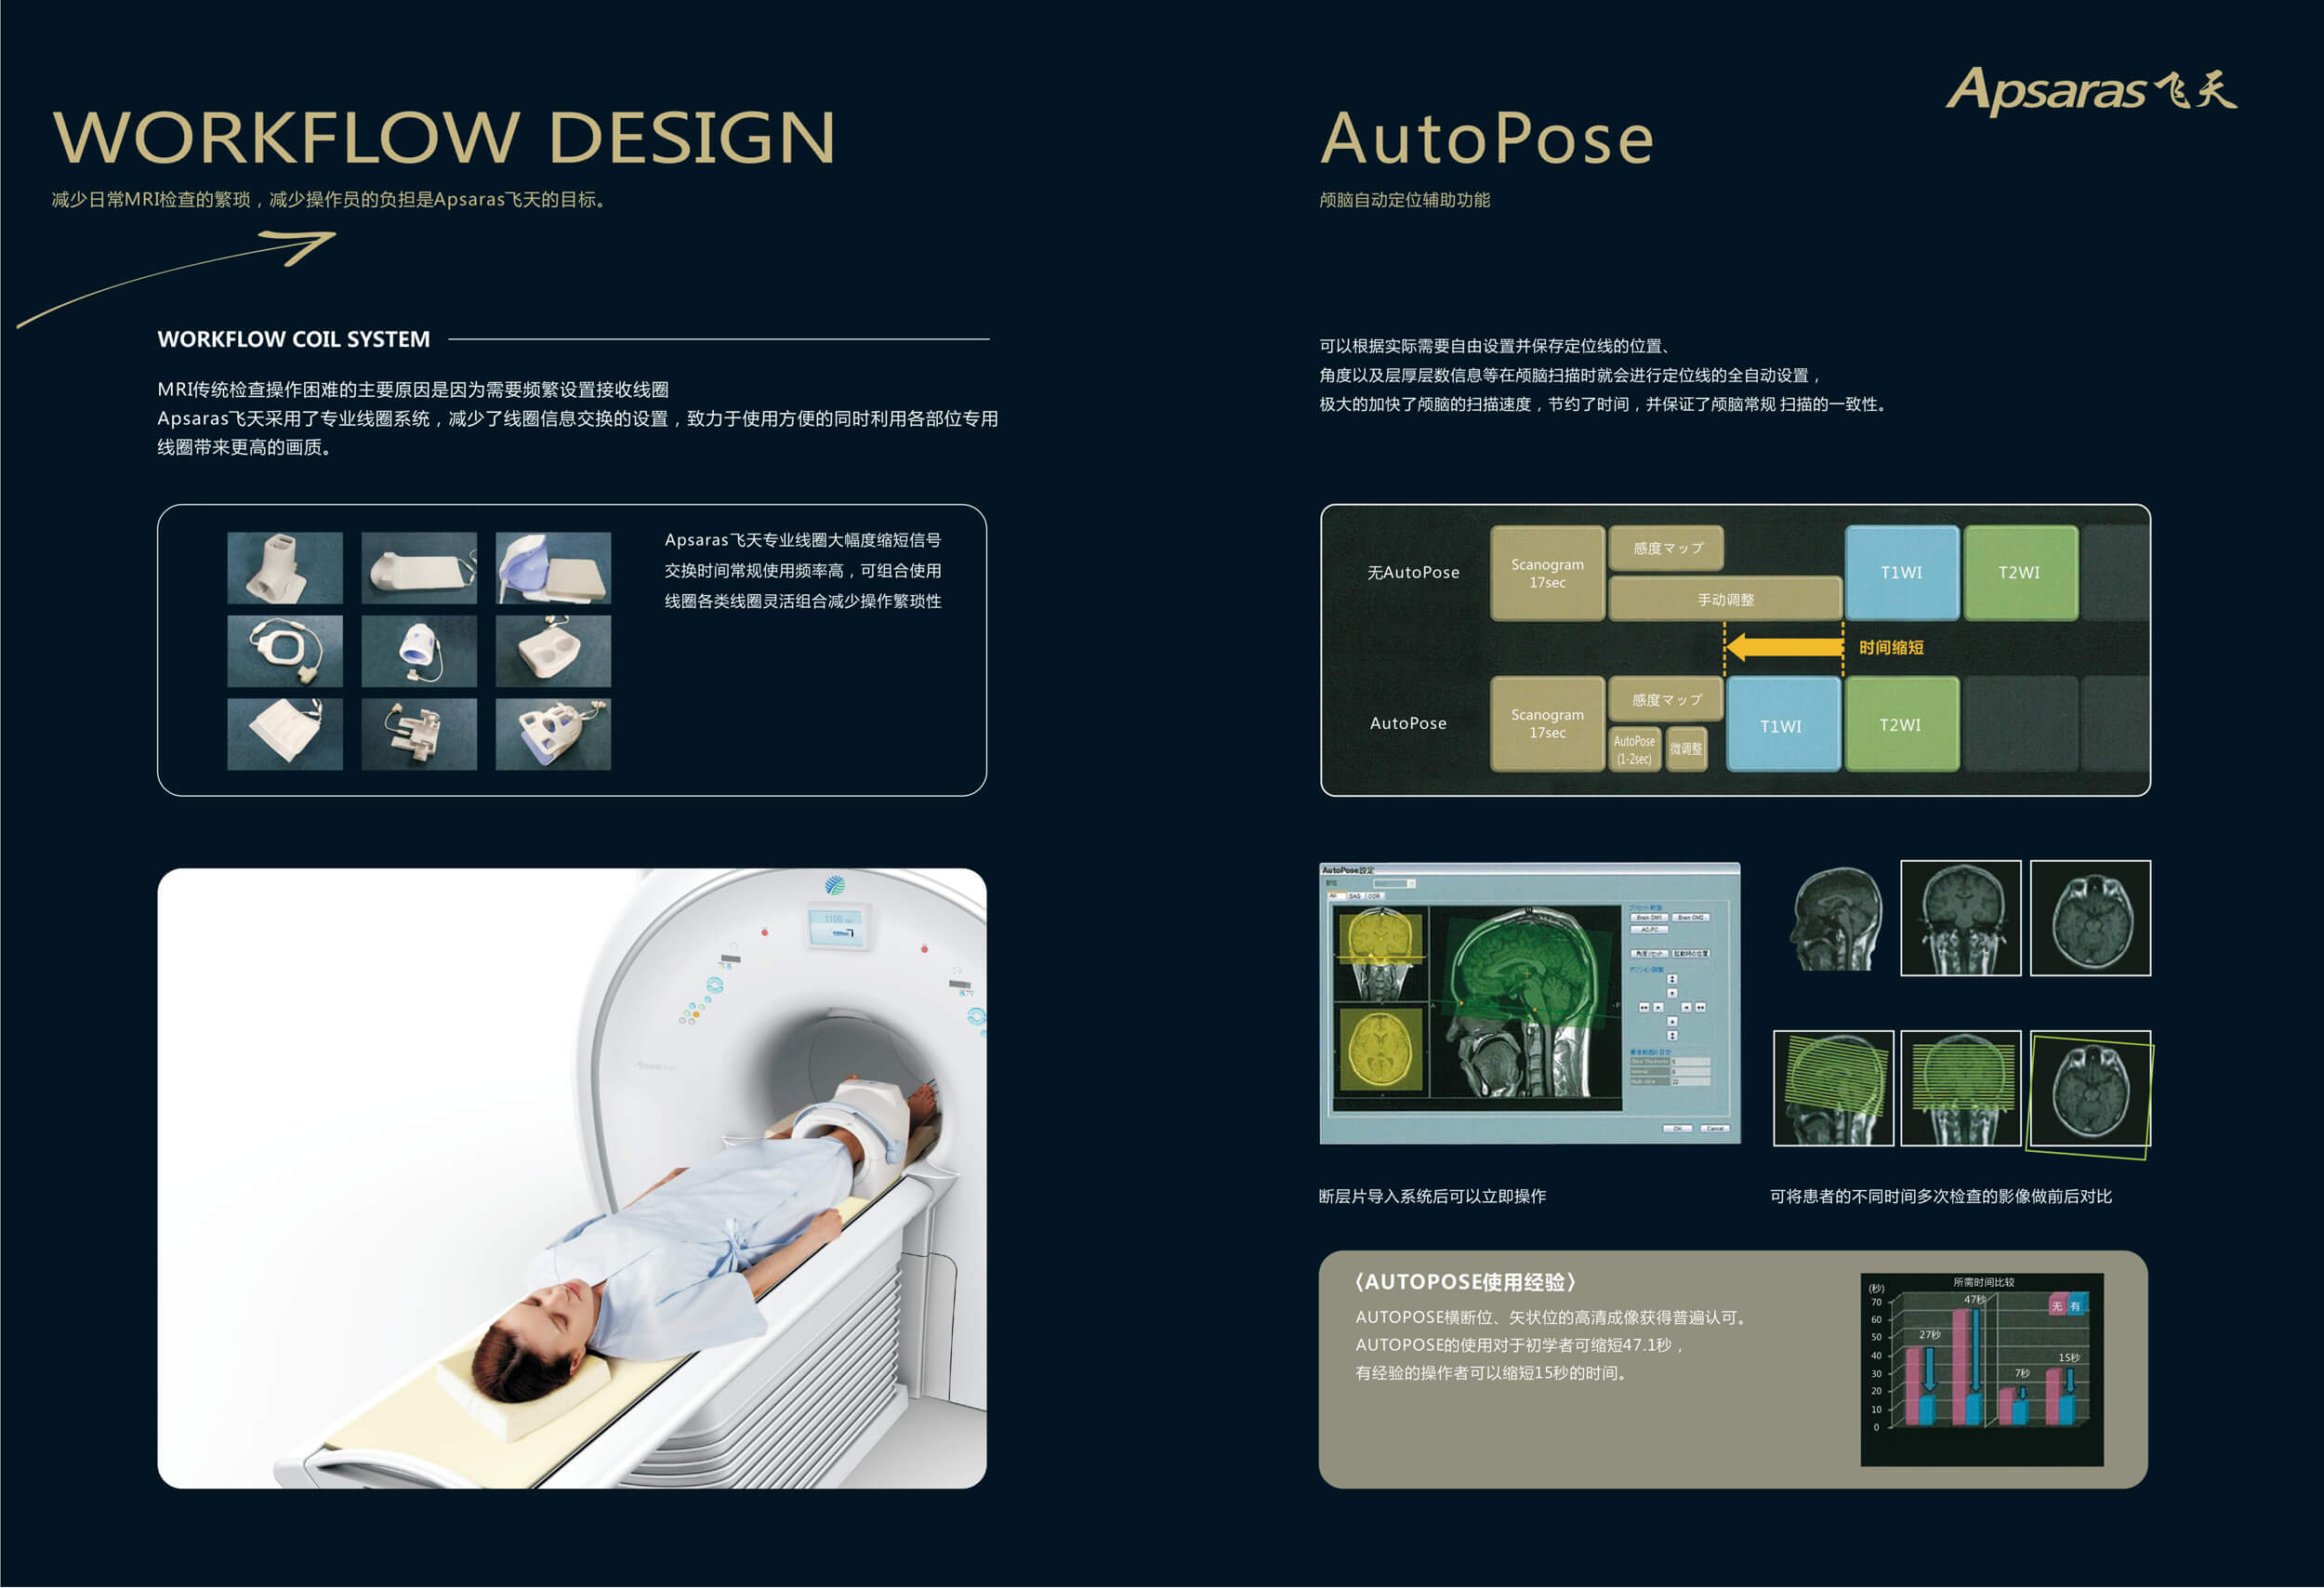

Apsaras飞天1 5t 超导核磁共振系统 先进技术 康达洲际医疗器械有限公司

Apsaras飞天1 5t 超导核磁共振系统 先进技术 康达洲际医疗器械有限公司